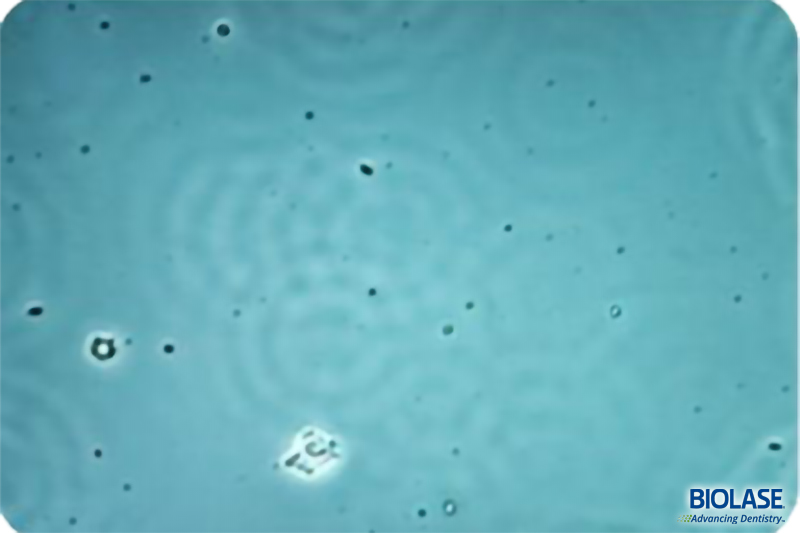

“Waterlase” 以字面上來解釋是水和雷射的結合,技術上的解釋是利用由 Er,Cr : YSGG 晶體釋放出特殊  2780nm 的雷射光源被水分子吸收結合,這個特殊波長的雷射可激發水分子而形成 “HydroPhotonics” 的能量,使水分子激發成為具有高速動能的狀態,利用水分子作為組織切割之媒介。

Erbium (鉺), Chromium (鉻): Yttrium (釔), Scandium (鈧), Gallium (鎵), Garnet (石榴石) = Er,Cr:YSGG = 2780 nm = 2.78 µm